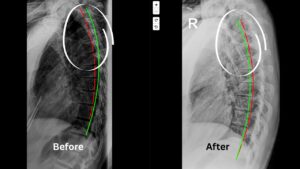

You can see from the above image of a before and after case, the change doesn’t have to be dramatic to have a big impact on your quality of life. This patient went from exercise induced asthma to breathing well with no problems with exercise and as you can see from the xrays, there was a little bit of over correction — which is never a bad thing because the forces that were pulling her down are still part of her life.